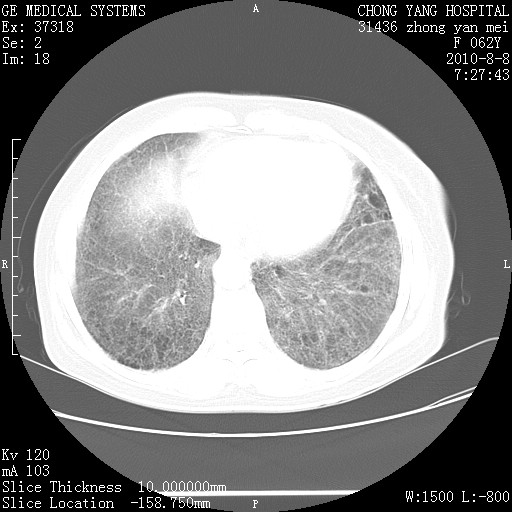

标题: CT28269:F62Y咳嗽胸痛数月。 [打印本页]

标题: CT28269:F62Y咳嗽胸痛数月。

两肺弥漫性间质纤维化伴继发性支扩。

考虑特发性肺间质纤维化

考虑两肺间质性肺炎并肺间质纤维化。

双肺间质纤维化合并感染、肺气肿

两肺间质纤维化并牵拉性细支气管扩张。

考虑两肺间质性肺炎并肺间质纤维化,肺气囊形成。

两肺间质改变,纵隔淋巴结肿大,需要考虑结节病的可能。